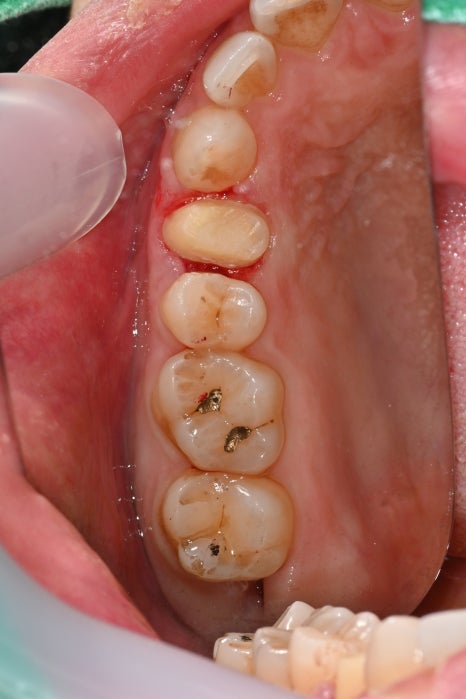

세 번째 사진: 초진 시 촬영한 하악(아랫니) 어금니 사진입니다. 아래 어금니 두 곳에서 충치가 진행되어 인레이 치료가 필요한 상태입니다.